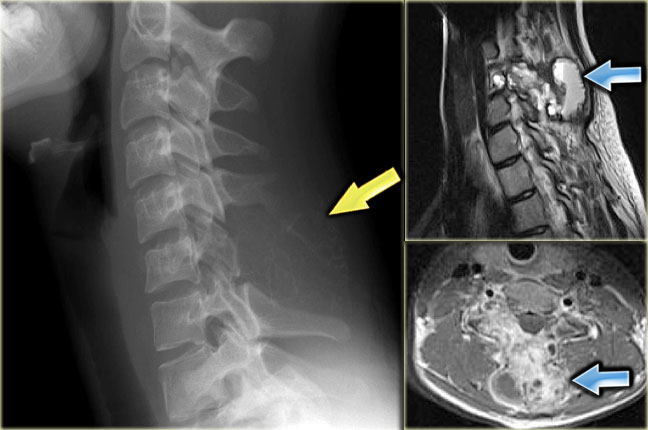

On the left a typical location for an ABC in the posterior elements of the spine.

Notice the well-defined osteolytic presentation with multiple fluid-fluid levels on MR with the patient in supine position.

The differential diagnosis based on the CT is:

ABC, Osteoblastoma and Tuberculosis (1).